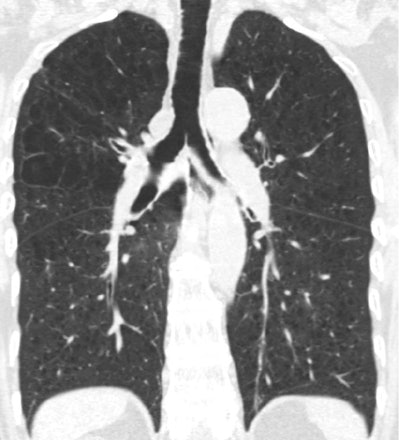

CT scan of lung showing emphysema. Image courtesy of Dr. Elizabeth Oelsner.MESA participants without airflow obstruction

Measures of airflow obstruction have been associated with mortality; however, emphysema is defined as air-space dilation due to parenchymal destruction. And while emphysema can be defined on histology, in practice it is CT attenuation that defines the disease (< -950 HU in this study).

The research team examined 2,985 MESA participants ages 45 to 84 years who did not have airflow obstruction on spirometry. They defined emphysema-like lung as the number of lung voxels with attenuation less than -950 HU on cardiac CT after adjusting for the number of total imaged lung voxels.